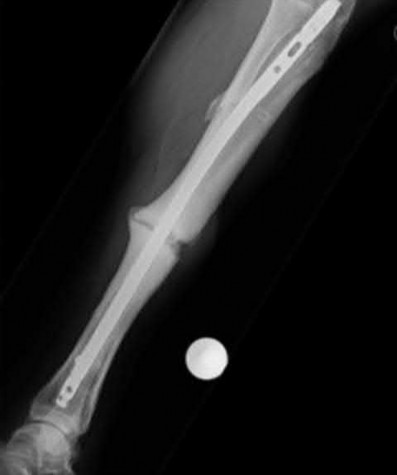

A 32-year-old male sustains a closed tibia fracture and develops intense leg pain out of proportion to the injury. You suspect acute compartment syndrome.

Which of the following pressure parameters is considered the most reliable threshold indication for performing a four-compartment fasciotomy?